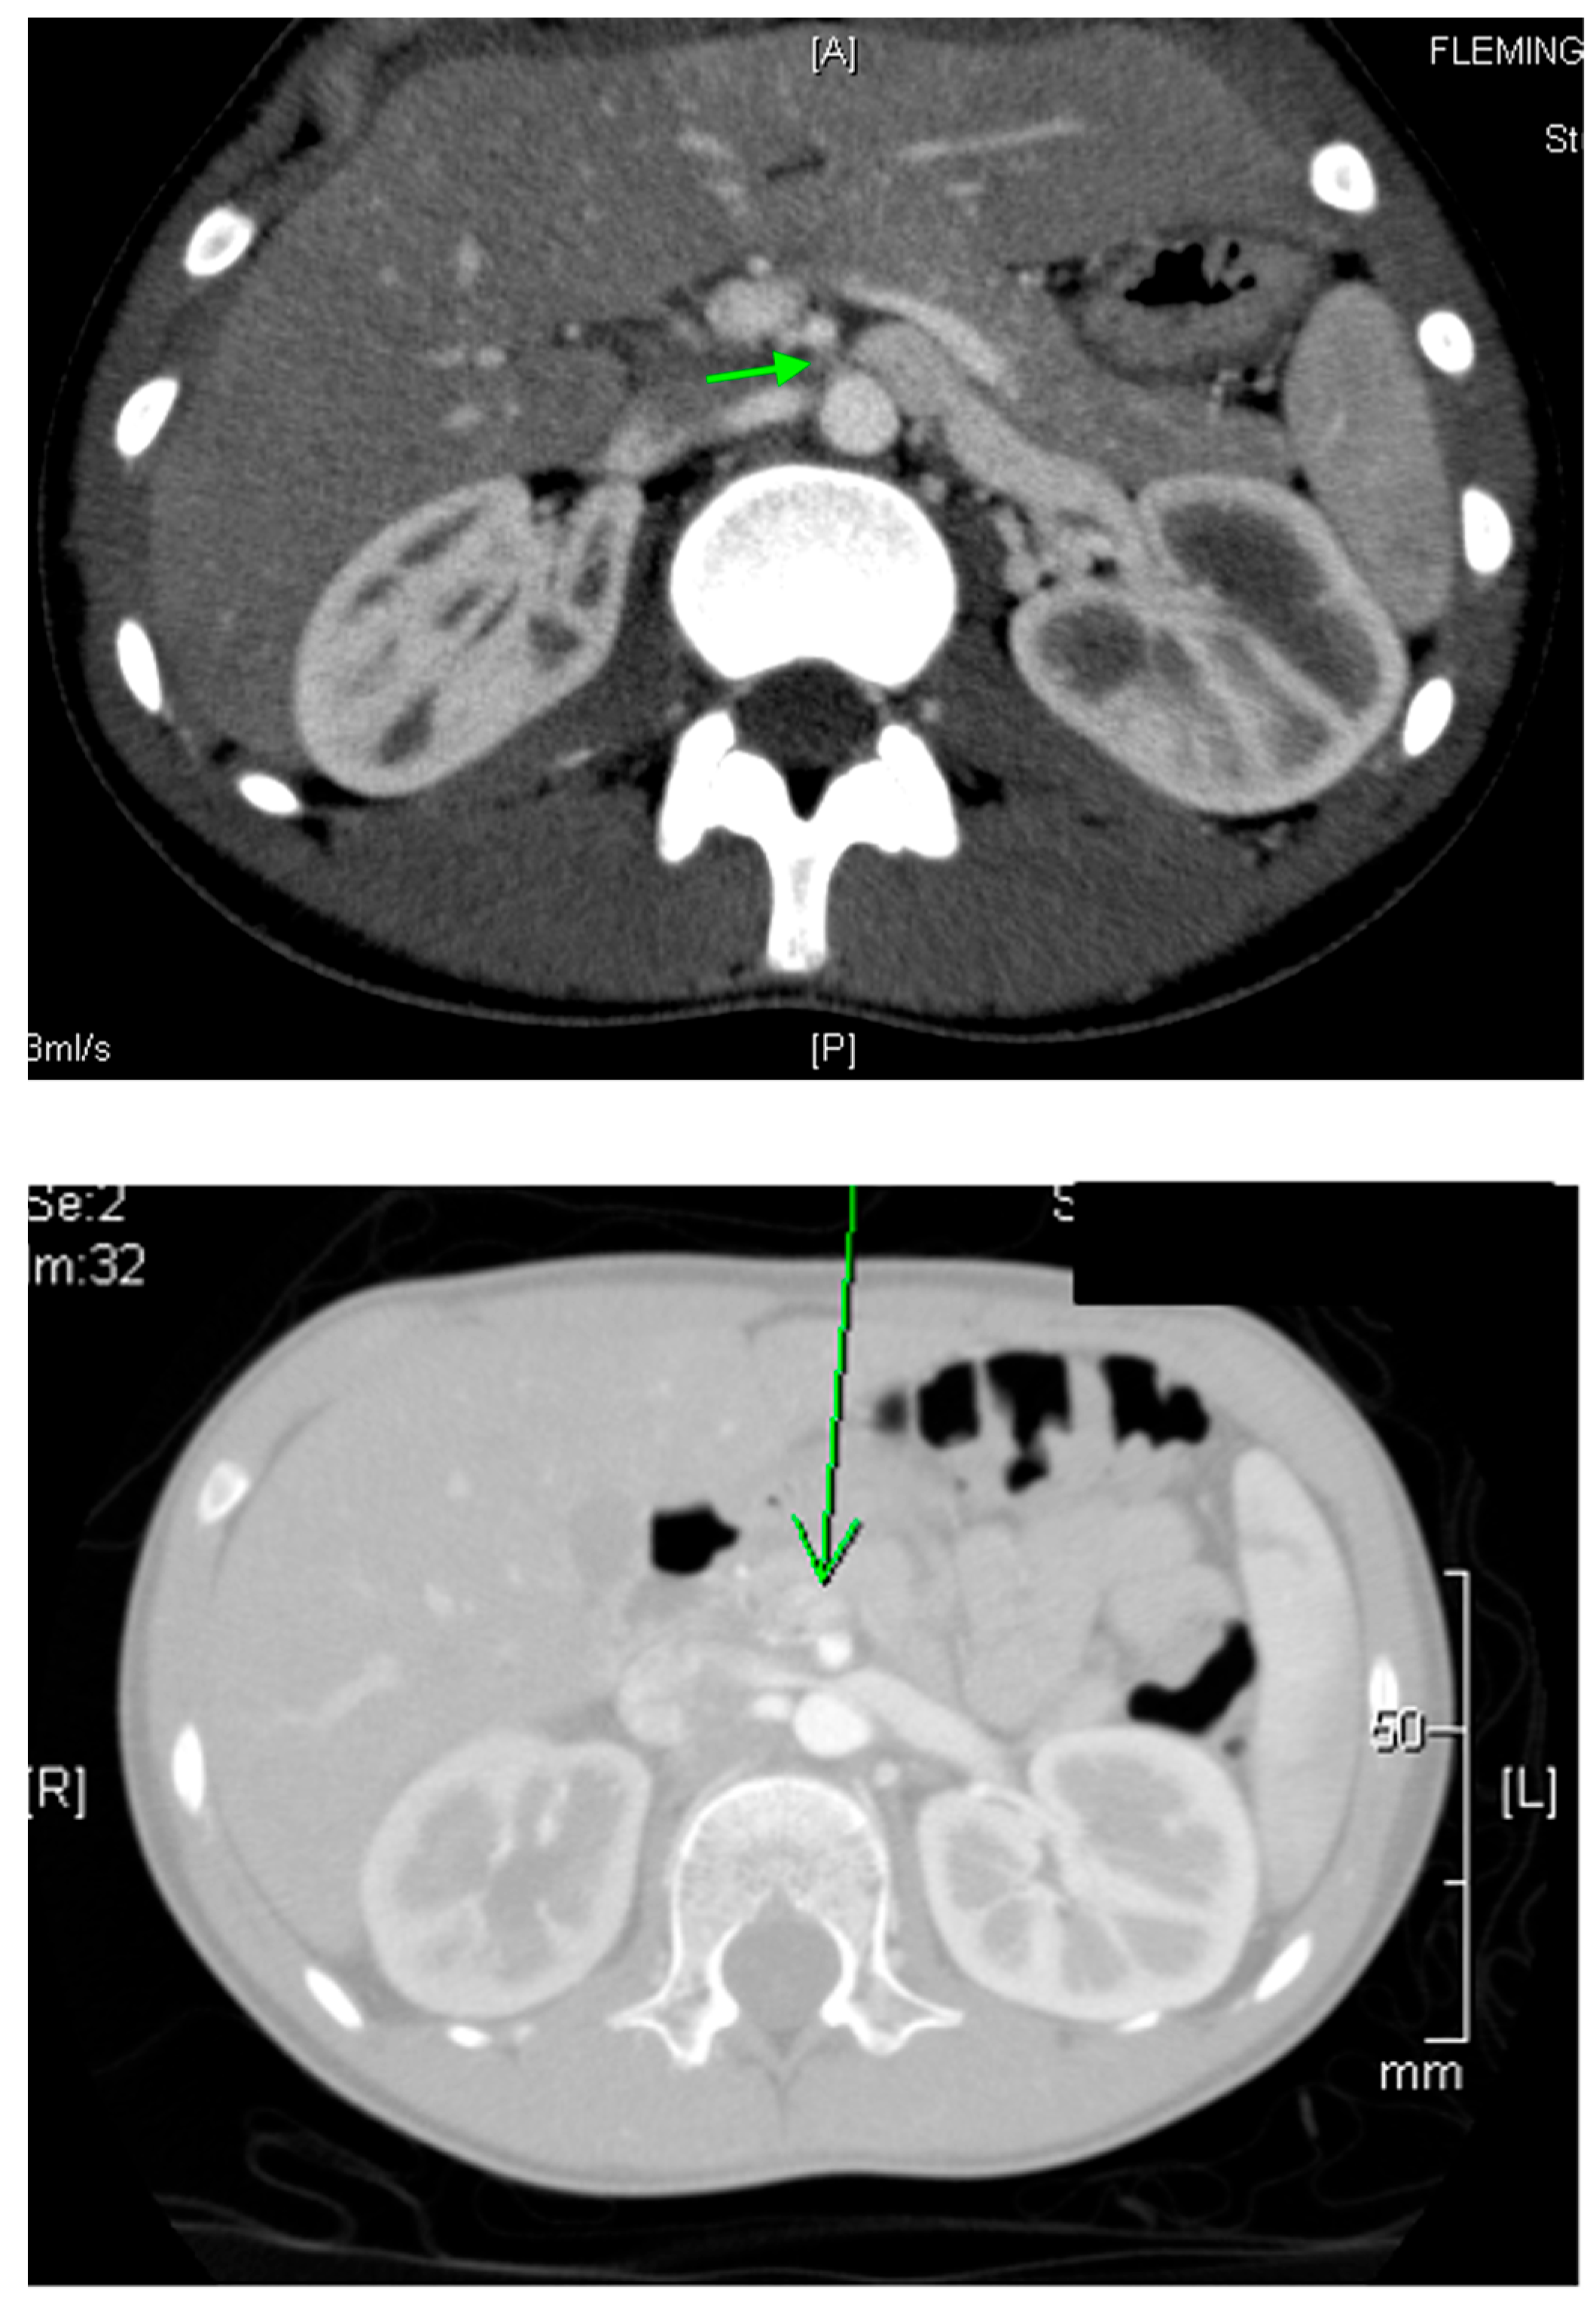

• A horseshoe kidney is the most common renal fusion anomaly, occurring in about 1 in 400 live births. In this condition, both kidneys are fused at their lower poles, forming a “horseshoe” shape (Figure 14)

• Renal ectopia occurs in approximately 1 in 900 births and is typically unilateral. In about 40% of cases, the ectopic kidney is located in the pelvis. Crossed ectopia occurs when one kidney crosses the midline and fuses with the other, often resulting in a “crossed-fused” appearance.

US is typically diagnostic for these conditions, as it can identify the location and structure of the kidneys. However, additional imaging, such as intravenous pyelography (IVP), CT, MRI, or renal scintigraphy, may be needed for further confirmation and to assess any associated abnormalities or complications (Figure 5).

Figure 14. A CT scan reveals a horseshoe kidney, with fusion of the lower poles indicated by green arrows.